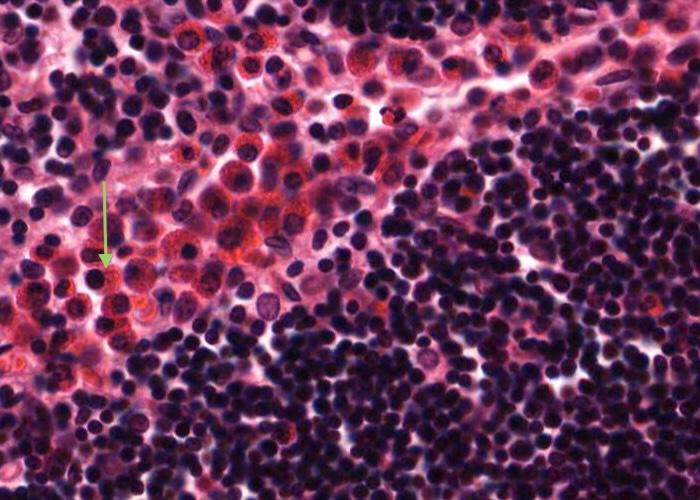

Mast cells with very prominent red-stained granules in their cyoplasm are common at the boundary of the thymus cortex and medulla.